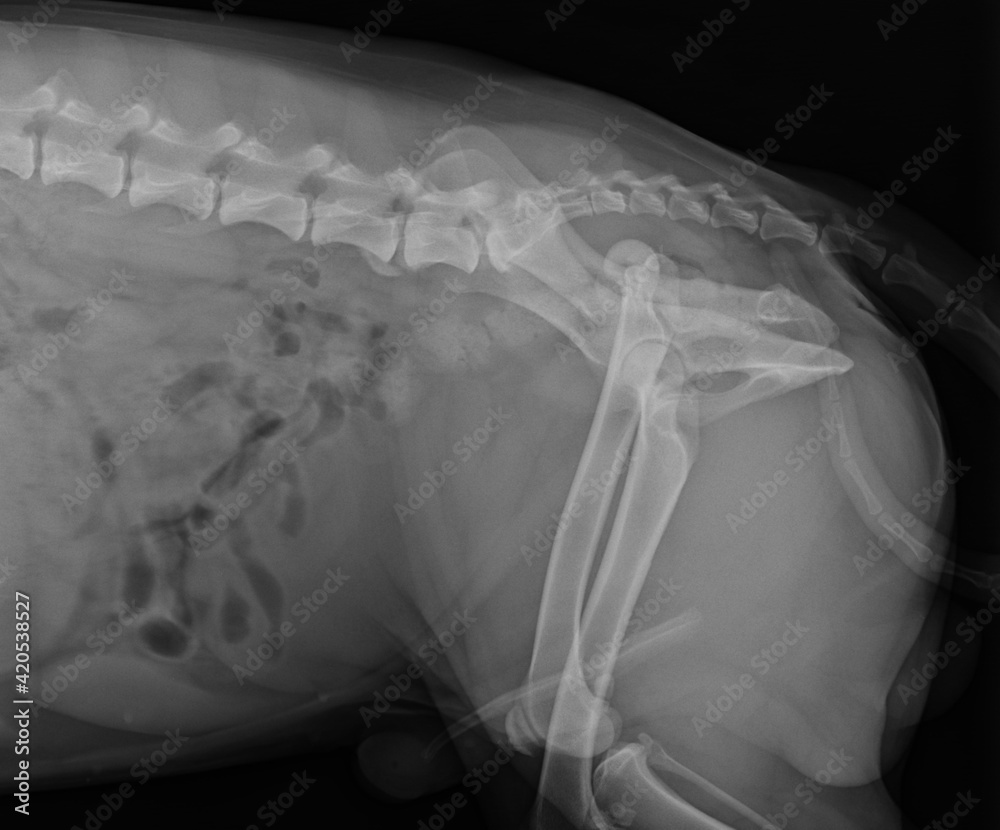

Foto Stock Dog X Ray Showing Hip Luxation Right Leg. Lateral View Hip Joint Luxation Dog when a dog has a dislocated hip, also known as a coxofemoral luxation, the ball part of the joint comes out of the socket. The ehmer sling flexes the hip joint and abducts and , dislocation produces disruption of the joint capsule and other supportive structures of the hip, including ligaments and often bone. physical examination findings. Hip Joint Luxation Dog.